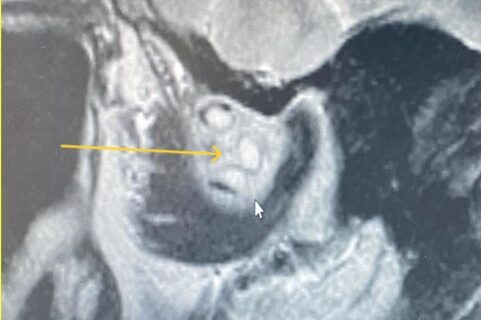

La diffusione metastatica del tumore polmonare alla regione condilare dell’articolazione temporo-mandibolare (ATM) presenta una serie complessa di sintomi e complicazioni, che possono influire significativamente sulla qualità di vita del paziente